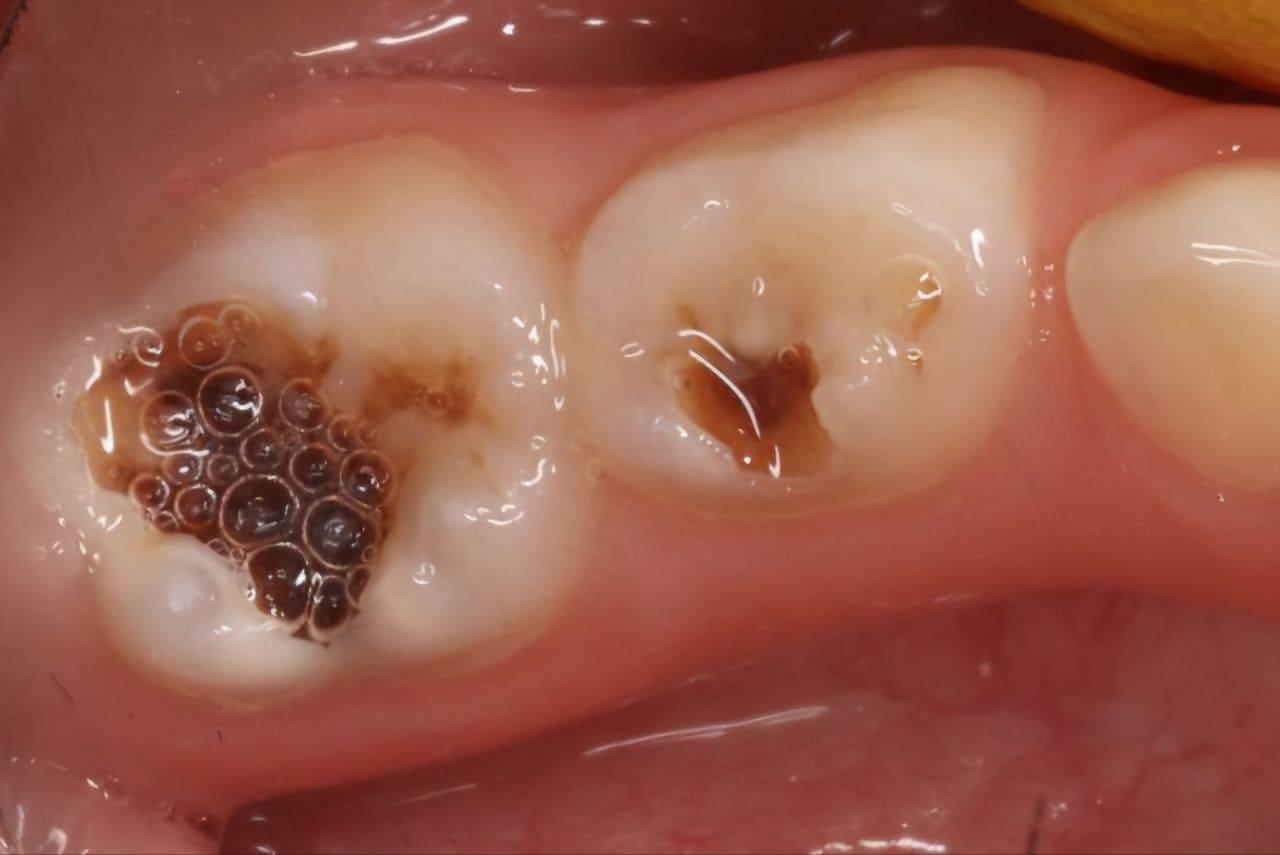

Поява перших постійних зубів, а це шості зуби, відбуваються, коли дитина ще не може, як слід провести їх гігієну та попіклуватись про їх здоров’я. Тому, на жаль вони і вражаються карієсом досить швидко. Пацієнт ще маленький – 6 років, а лікування потребує дорослого: зі знеболенням та ізоляцією. Саме таке і було проведене в даному випадку: зуб очищений від інфікованих тканин, відновлений фотополімерним матеріалом і готовий довго служити юному господарю.